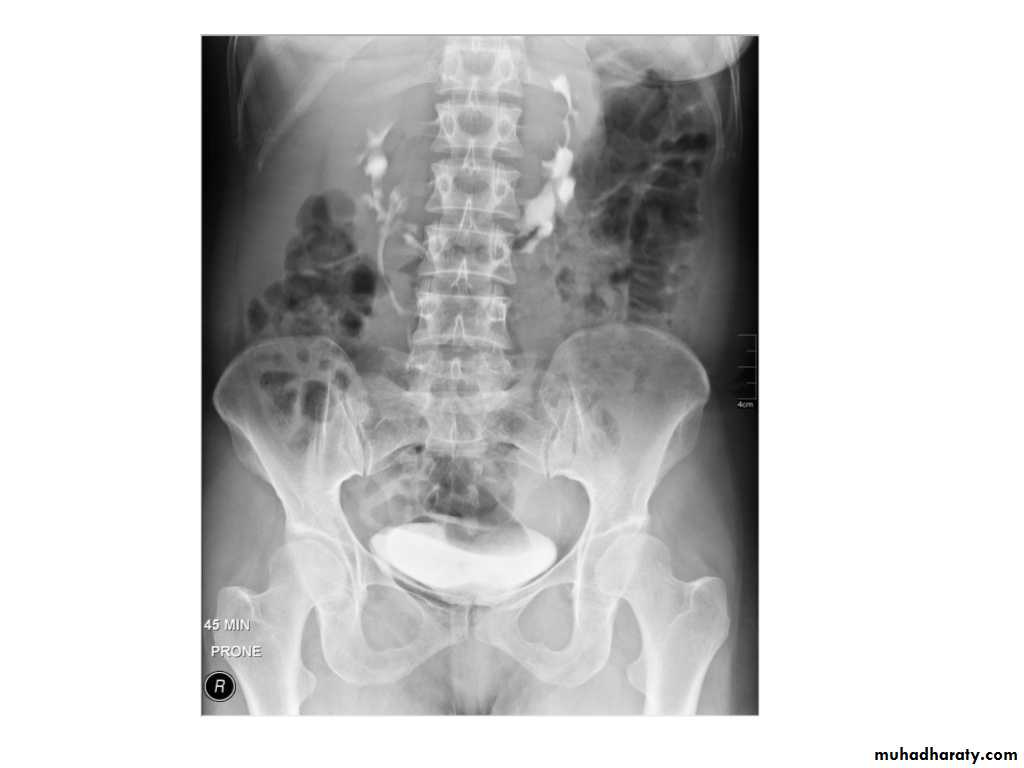

IVU shows

1. The kidneys at low position .2.Close to the spine with long axis parallel to the spine

3. Malrotation manifested by medially directed calyces.

4- The renal pelvis and ureters are anterior and lateral in position.

5- Hydronephrosis and calculi highly associated.